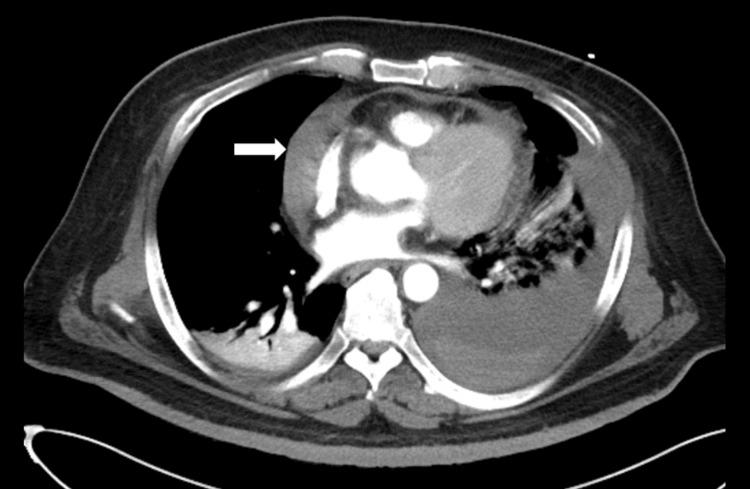

Background The objective of this study was to assess the efficacy of a computed tomography (CT) scan of the chest in detecting structural cardiac and pericardial injuries. Methods We retrospectively analyzed data from a data registry at a trauma center between January 2015 and June 2022. This study included individuals with severe chest trauma (defined as an Abbreviated Injury Scale score of ≥3 for the chest). The assessment of cardiac injury from chest CT scans relied on the information provided in the official radiological reports. Definitive diagnoses of structural cardiac injury were confirmed on the basis of surgical findings or the diagnosis upon discharge. Results The chest CT scans revealed 11 cases of pericardial abnormalities: 10 (90.9%) cases of pericardial effusion in patients with blunt trauma and one (9.1%) case of pneumopericardium in a patient with a stab wound. Among these 11 cases, surgical exploration identified four structural cardiac and pericardial injuries, and three died during hospitalization. The remaining seven cases underwent nonsurgical intervention, and none exhibited any cardiac and pericardial abnormalities. The chest CT for traumatic structural cardiac and pericardial injuries had a sensitivity of 4/4 (100.0%), a specificity of 402/411 (97.8%), a positive predictive value of 4/11 (36.4%), and a negative predictive value of 404/404 (100.0%). Conclusion This study highlighted a high mortality rate among patients diagnosed with structural cardiac injuries, underscoring the critical importance of accurate and timely diagnostic investigations in such cases. Our findings confirmed that chest CT is a reliable screening tool for detecting structural cardiac injuries in patients with both blunt and penetrating chest trauma. However, given the relatively low positive predictive value of chest CT for structural cardiac injuries, additional diagnostic imaging or prompt surgical intervention may be necessary in cases where pericardial abnormalities are identified on chest CT to address potential occult cardiac injuries.

背景 本研究的目的是评估胸部计算机断层扫描(CT)在检测心脏和心包结构损伤方面的有效性。方法 我们回顾性分析了2015年1月至2022年6月期间一家创伤中心数据登记处的数据。本研究纳入了严重胸部创伤患者(定义为胸部简略损伤量表评分≥3)。胸部CT扫描对心脏损伤的评估依赖于官方放射学报告中提供的信息。心脏结构损伤的明确诊断基于手术结果或出院时的诊断。结果 胸部CT扫描显示11例心包异常:钝性创伤患者中有10例(90.9%)心包积液,刺伤患者中有1例(9.1%)心包积气。在这11例中,手术探查发现4例心脏和心包结构损伤,3例在住院期间死亡。其余7例接受非手术干预,均未出现任何心脏和心包异常。胸部CT对创伤性心脏和心包结构损伤的敏感性为4/4(100.0%),特异性为402/411(97.8%),阳性预测值为4/11(36.4%),阴性预测值为404/404(100.0%)。结论 本研究强调了诊断为心脏结构损伤的患者死亡率较高,突显了在此类病例中准确及时的诊断性检查的至关重要性。我们的研究结果证实,胸部CT是检测钝性和穿透性胸部创伤患者心脏结构损伤的可靠筛查工具。然而,鉴于胸部CT对心脏结构损伤的阳性预测值相对较低,在胸部CT发现心包异常的病例中,可能需要额外的诊断性成像或及时的手术干预,以处理潜在的隐匿性心脏损伤。